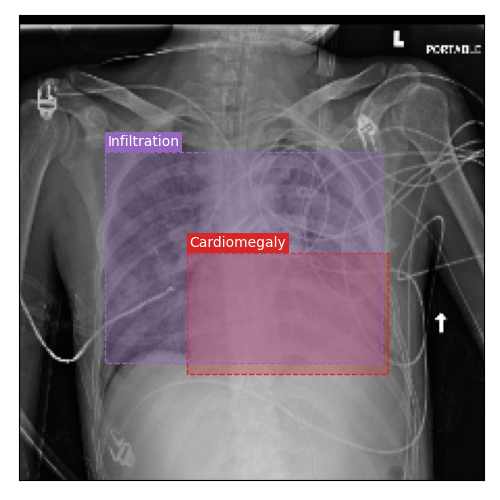

Qualitative Results

As shown in Fig. 4 Loc-ADPD detects cardiomegaly almost perfectly, as it is always exactly localized at one anatomical region. Other pathologies are detected but often with too large or too small boxes as they only cover parts of anatomical regions or stretch over several of them, which cannot be completely corrected using WBF. Detection also works well for predicting several overlapping pathologies. For qualitative comparisons between Loc-ADPD and MIL-ADPD, we refer to Appendix 0.B.

Appendix 0.B Qualitative Results and Failure Cases

| Loc-ADPD | MIL-ADPD | Loc-ADPD | MIL-ADPD |

![]() |

| (a) | (b) | ||